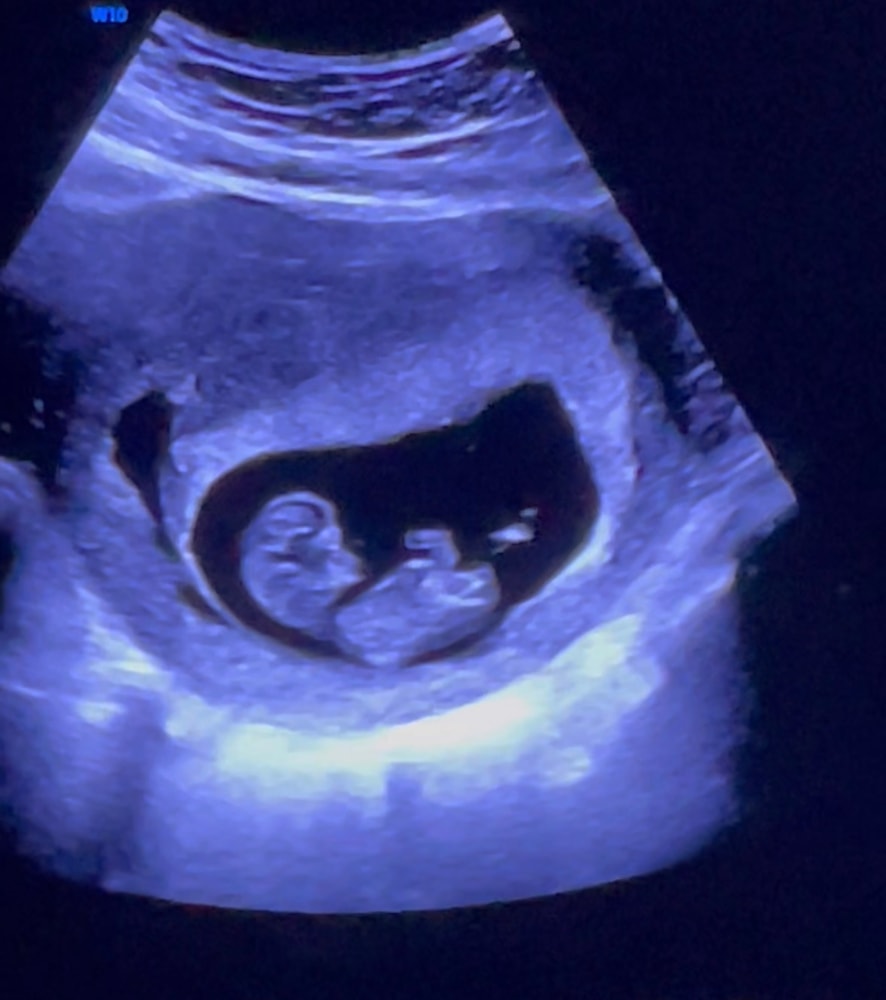

у нас все хорошо, развивается малыш по сроку , во вторник пойду на 1 скрининг , но в 11 недель ( неделю назад) была на узи , наш малыш вертелся , дрыгал ручками и ножками во всю ❤️☺️такое счастье , пусть и дальше так будет хорошо все.(интересно кто там сидит 💙 или 💜)

хотя пару дней назад поссорились с мужем и я сильно нервничала , но когда сильно нервничаю беру в руки доплер , нахожу сердечко малыша и успокаиваюсь , фото на память !

тут 10+6-11 недель 🥹